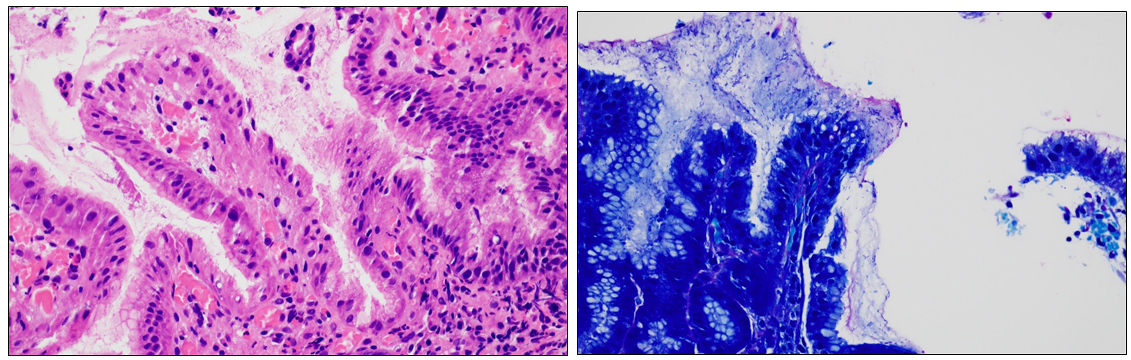

55세 남자가 속이 쓰려 위 내시경 검사를 받았다. 위 조직 검사의 H&E 염색 소견(왼쪽 사진)과 김자(Giemsa) 염색 소견(오른쪽 사진)이다. 진단은?

[헬리코박터 위염]

• 위 내시경 검사 후 조직의 김자(Giemsa) 염색 소견에서 확인할 수 있는 세균은 헬리코박터 파일로리(Helicobacter pylori)이다.

• 김자 염색은 헬리코박터 파일로리의 존재를 확인하기 위한 특별한 염색법으로, 이 세균은 위염, 위궤양, 십이지장궤양, 그리고 위암과 연관성을 보인다.